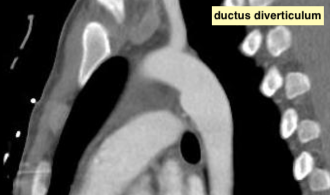

- il peut créer une éctasie de l’aorte en sagittal (diverticule ductal = ductus diverticulum à ne pas confondre avec le diverticule de Kommerell !)

DD entre pseudoanévrisme traumatique et diverticule ductal

- Le diverticule ductal a un raccordement plutôt obtus

- Le pseudoanévrisme trauamtique à un raccordement plutôt aigu

Ductus Diverticulum